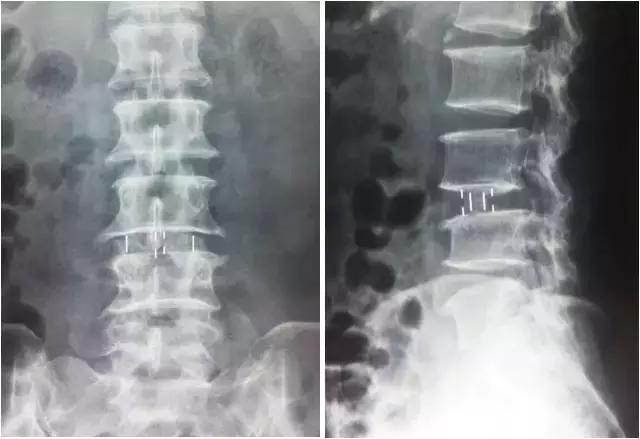

▲手术后

微创治疗真性腰椎滑脱症

▲手术前

▲手术后X线平片